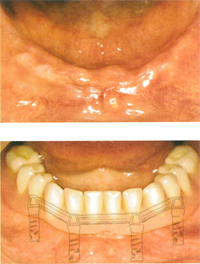

【歯がまったくない場合】

下顎の歯が1本も無い場合の修復にはインプラントがよく利用されます。

インプラントのヘッド部をバー状の維持装置で連結し、その上に取り外し式の入れ歯をしっかりと固定することができます。